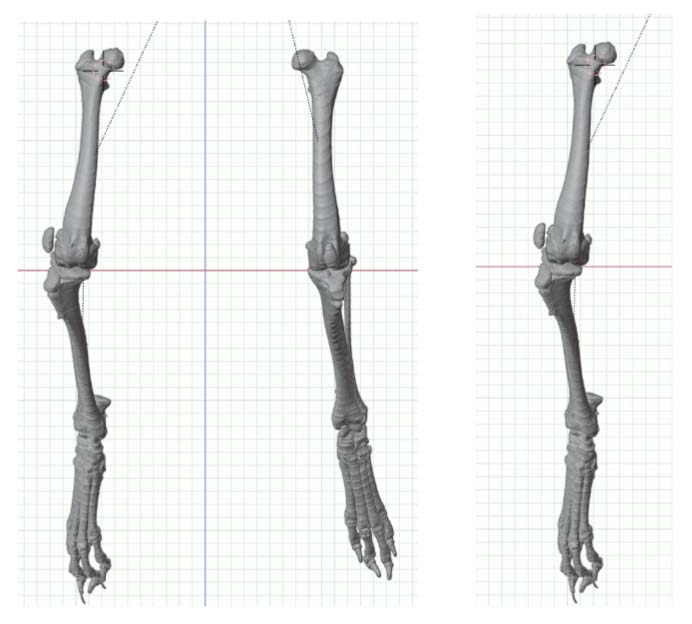

Accurate surgical planning for such severe deformities benefit from additional diagnostics, such as cross-sectional imaging, which was recommended and performed.

Pelvic limb computed tomography (CT) scan for computer-aided design (CAD)-based surgical planning was performed readily with sedation.

A method of planning and correction, commonly used in human surgery, has been adapted for the small-animal patient. This method is called the center of rotation of angulation (CORA). With this method, bone axes and joint orientation angles were made to provide guidance for accurate correction of angular limb deformities based on one standard set of geometric principles as they apply to osteotomies, regardless of the bone in question or the type of fixation device.

CT CAD-based approach to deformity planning documented two right femoral deformities:

Excessive anatomical lateral distal femoral angle (aLDFA) = 88.8 degrees

Femoral version 20 degrees

One right tibial deformity (19 degrees of excessive tibial internal torsion)

CT CAD-based surgical plan.